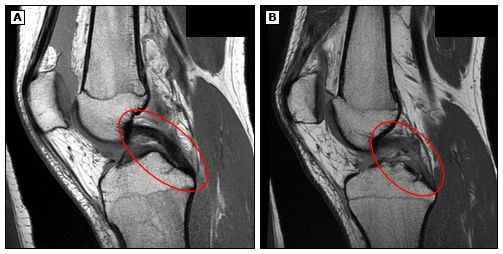

(Слева) На осевой МРТ PDВИ определяется полный разрыв сухожилия подлопаточной мышцы. Кроме того, имеется медиальный вывих сухожилия длинной головки двуглавой мышцы и пустая межбугорковая борозда.

(Справа) На фронтальной косой МРТ Т2ВИ FS у этого же пациента виден полный разрыв сухожилия надостной мышцы по толщине, разрыв сухожилия подлопаточной мышцы и вывихнутое сухожилие двуглавой мышцы. У двух третей пациентов с разрывом сухожилия подлопаточной мышцы также имеется разрыв сухожилия надостной мышц, обычно захватывающий переднюю часть сухожилия.